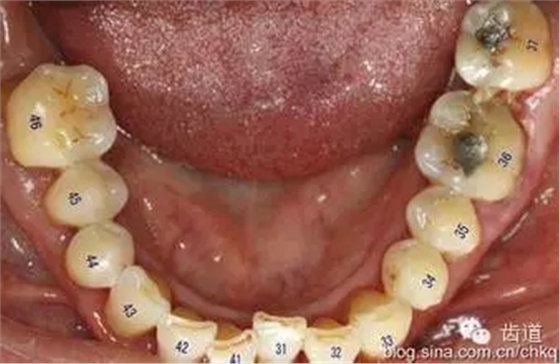

8、根分叉病變的檢查

根分叉病變是指牙周炎發(fā)展到較重的程度后,病變累及多根牙的根分叉區(qū),它可發(fā)生于任何類型的牙周炎。下頜第一磨牙患病率最高,上頜雙尖牙患病率最低。發(fā)生率隨年齡增大而上升。

操作方法: 用普通的彎探針或?qū)iT設(shè)計(jì)的Nabers探針探查多根牙的分叉區(qū)。檢查上頜磨牙時(shí),先探查頰側(cè)中央處的根分叉區(qū),再從腭側(cè)分別探查近中和遠(yuǎn)中的根分叉區(qū),但有的會(huì)有變異,需從頰側(cè)探入;檢查下頜磨牙時(shí),從頰側(cè)和舌側(cè)中央處分別探查根分叉區(qū)。探查的內(nèi)容應(yīng)包括:探針能否水平方向探入分叉區(qū),水平探入的深度,分叉的大小,有無釉質(zhì)突起,根柱的長(zhǎng)度,根分叉區(qū)是否有牙齦覆蓋,注意檢查根分叉區(qū)是否暴露。 SEE MORE →

牙周袋和骨吸收波及根分叉區(qū),可從臨床上探查到。主要根據(jù)探診和X線片來判斷病變的程度。Glickman將其分為四度,此分類法有利于指導(dǎo)治療和判斷預(yù)后。

Ⅰ度:從牙周袋內(nèi)已能探到根分叉的外形,但尚不能水平探入分叉內(nèi),在X線片上看不到分叉區(qū)牙槽骨的吸收醫(yī)`學(xué)教育網(wǎng)搜集整理。

Ⅱ度:分叉區(qū)骨吸收僅限于頰側(cè)或舌側(cè),或頰舌側(cè)均有吸收但尚未與對(duì)側(cè)相通,根分叉區(qū)內(nèi)尚有部分牙槽骨和牙周膜存在。臨床探查時(shí)探針可從水平方向部分地進(jìn)入分叉區(qū)內(nèi),但與對(duì)側(cè)不相通,X線片一般僅顯示分叉區(qū)的牙周膜增寬,或骨質(zhì)密度有小范圍的降低。

Ⅲ度:根分叉區(qū)的牙槽骨全部吸收,形成“貫通性”病變,探針能水平通過分叉區(qū),但它仍被牙周袋軟組織覆蓋而未直接暴露于口腔。下頜磨牙的Ⅲ度病變?cè)赬線片上可見完全的透影區(qū),但有時(shí)會(huì)因牙根靠近或外斜線的重疊而使病變不明顯。

Ⅳ度:根間骨隔完全破壞,且牙齦退縮而使病變的根分叉區(qū)完全暴露于口腔。X線片所見與Ⅲ度病變相似。